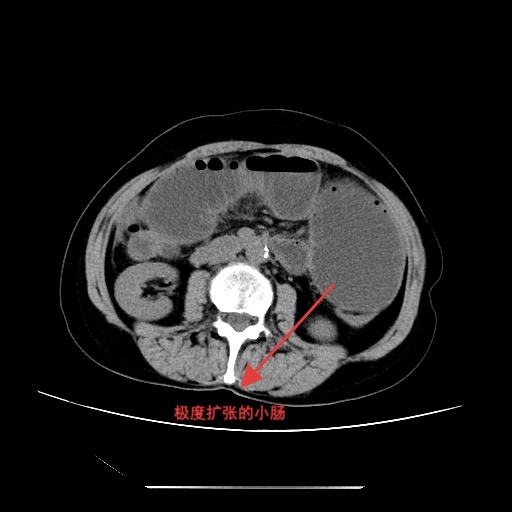

▲肠梗阻导管置管后影像所见

入院后,完善相关检查,腹部立位平片提示肠管扩张,可见多个液气平面,结合病史考虑术后肠梗阻。经综合评估,决定先行保守治疗,在胃肠外科和疝外科刘奇副主任医师团队协作下,为患者置入肠梗阻导管。置管后,患者腹胀、腹痛症状明显缓解,胃肠减压引流通畅,肠鸣音逐渐恢复。经精心护理及营养支持,患者肛门排气排便恢复正常,复查腹部平片示肠管扩张较前明显改善,无液气平面。病情持续好转,顺利出院。